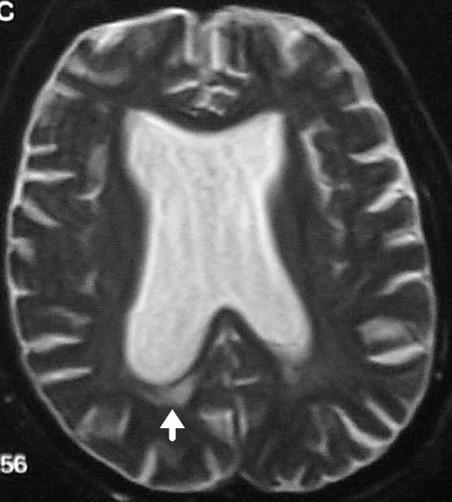

what type of imaging is this and what is being shown

MRI: water dense in MRI

arrow poniting to periventricular damage, which is more likely with high pressure hydrocephalus

would dilated ventricles at autopsy signal hydrocephalus

YEP